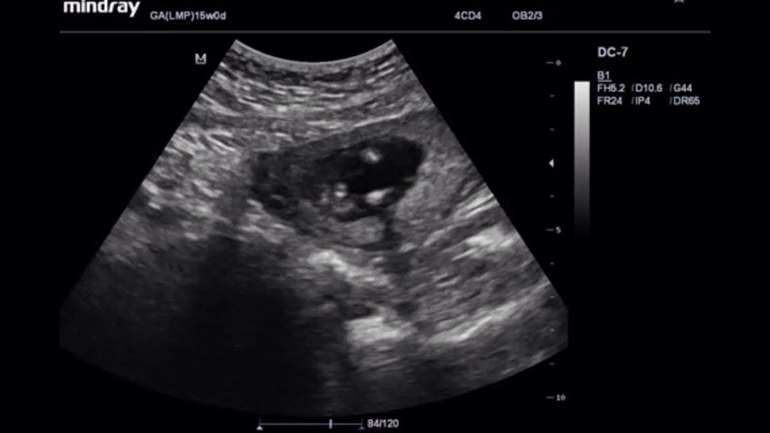

Мальчик или девочка? Как считаете?узи 15-16 недель,отдалено правда на фото:(

У меня в 16 недель на экране тоже были 2 полоски, предположили девочку, в 20 подтвердили, у вас плоховато видно...вам узист не предположил кто?

Врач очень сомневаясь предположила мальчика,но сказала что весьма не точно)

Ну вот и мне в 16 предположила с сомнением, подождите месяц и узнаете точно!

а там головы и не видно,вид снизу,чисто ножки и попка))